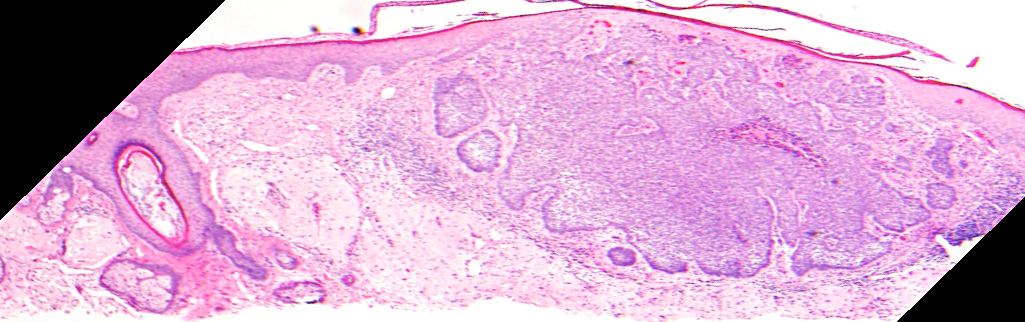

VA94: Right Forehead, Basal Cell Carcinoma, Nodular

- * denote hyporeflective nest structures, arrows indicate bands of collagen compression between adjacent nests